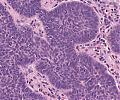

A82 Appendix-Karzinoid

Große, nestartige Verbände neuroendokriner Tumorzellen

A82 Appendix-Karzinoid

Tumorzellnester und diffuse Infiltration der neuroendokrinen Tumorzellen

Appendixkarzinoid

Erkennbar sind isomorphe Tumorzellnester

Appendixkarzinoid

Neuroendokriner Tumor mit nestartigen, trabekulären Formationen isomorpher Tumorzellen